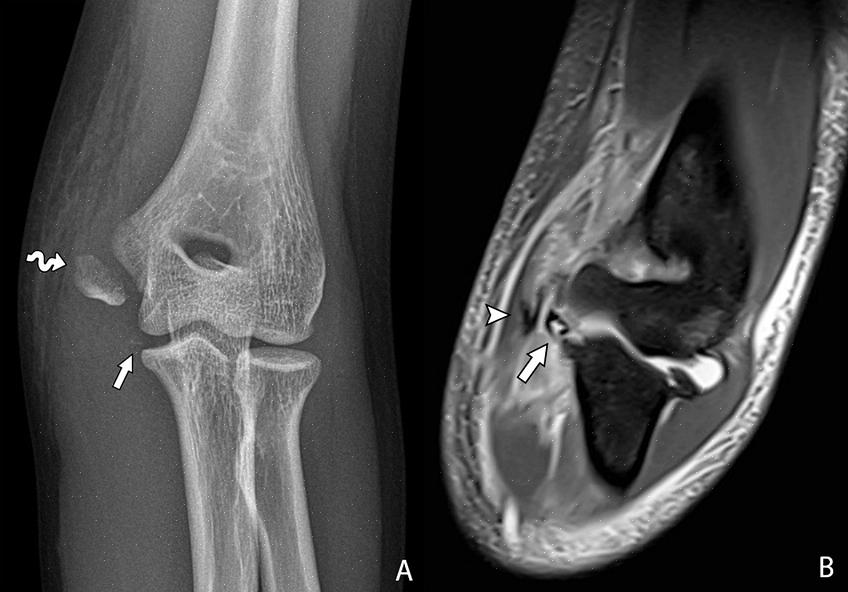

בדרך כלל, רופא יזהה כל נזק באמצעות טכניקות כגון רדיוגרפיה, טומוגרפיה או הדמיית תהודה מגנטית גרעינית. זו האחרונה היא אולי השיטה המדויקת ביותר שבה הרופא יוכל לראות את הנזק בפירוט רב יותר.